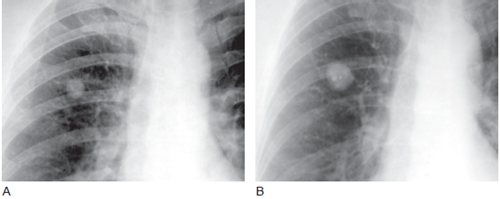

肺错构瘤的影像病例欣赏 华夏影像诊断中心 2019-01-07 02:45 来源:百度文库 相关推荐 换一换 为您推荐了10篇文章,点击查看

1.肺错构瘤 肺错构瘤大多数为良性,恶性仅占0.5%左右,但是文献也有肺错构瘤恶变的报道。由于本部有时难于与周围型肺癌鉴别,因此多主张早期手术。对中、老年人肺部孤立